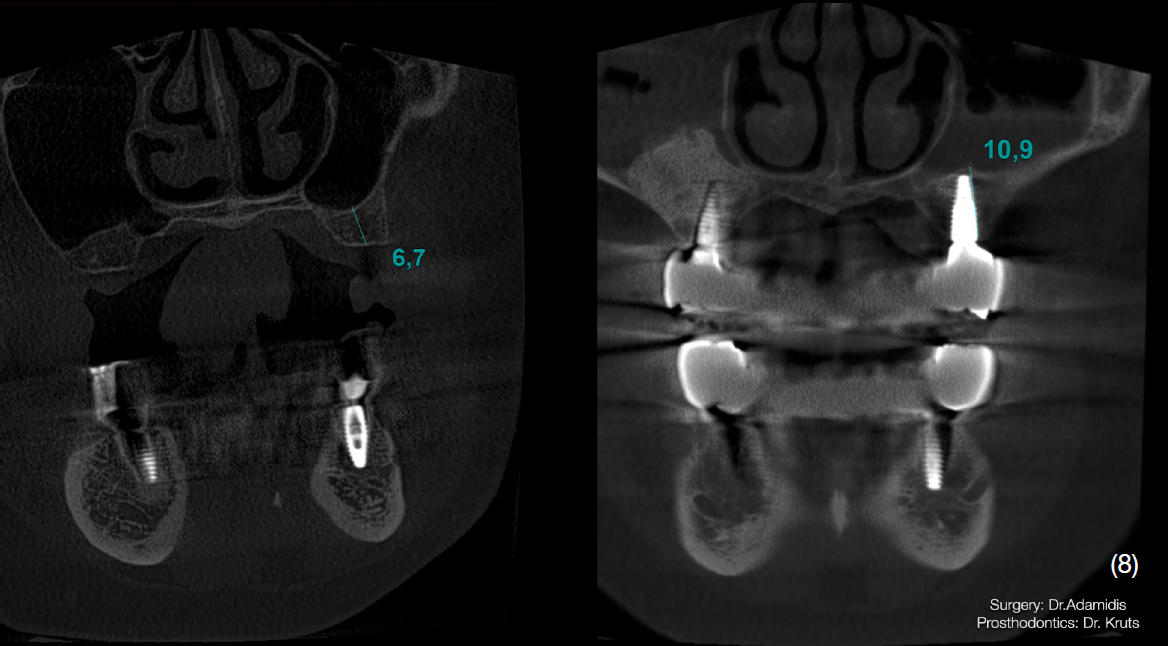

Після детального вивчення даних комп’ютерної томографії пацієнта, було затверджено план лікування, який складався із двох хірургічних етапів.

Через 3 місяці після першого етапу було проведено операцію на верхній щелепі. Було виконано відкритий синус-ліфтинг в першому квадранті та закритого в другому.

Матеріалом, що використовувався під час операції був Straumann Xenograft та аутологічна кістка, яка була забрана із ділянки зовнішньої косої лінії.

Одномоментно з кістковою аугментацією встановлено імплантати Strauman BLT діаметром 3.3mm в ділянках 12, 15, 17, 23, 25 зубів. Операційну рану було ушито, зворотньо зафіксовано тимчасову конструкцію на наявних зубах.